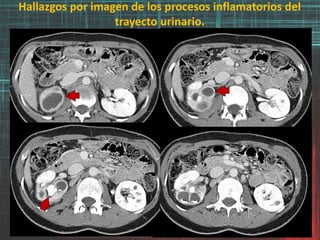

FASE SIMPLE FASE ARTERIAL

FASE VENOSA FASE EXCRECION

♀ con dolor abdominal inespecífico. Se envía a TC para su estudio.